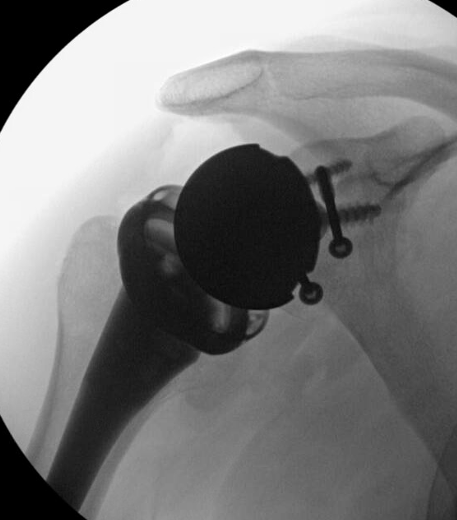

Reverse TSA +/- glenoid bone graft

Chronic locked with large Hill Sachs treated with rTSA + glenoid bone graft

Chronic locked with large Hill Sachs and normal glenoid treated with rTSA + glenoid bone graft